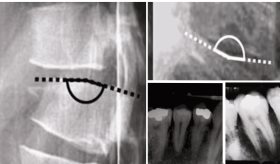

Esta última reveló un sistema coronario derecho dominante, sin lesiones ateroscleróticas obstructivas y una fístula coronaria originada en la porción distal de la arteria descendente anterior, con drenaje hacia el ventrículo izquierdo.

Las imágenes angiográficas mostraron claramente la extravasación del medio de contraste desde la arteria hacia la cavidad ventricular (figuras 2 y 3), lo cual explicaba la sintomatología del paciente.